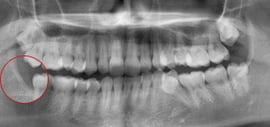

右下の親知らずが度々腫れるとのことで来院された状態です。 手前の歯にロックされていて横に向いている親知らずが生えることができません。

お口の中を一旦きれいに清掃し、お薬にて腫れを落ち着かせた状態にしてから親知らずを抜歯します。

平均しておおよそ10分~20分程度の処置時間です。